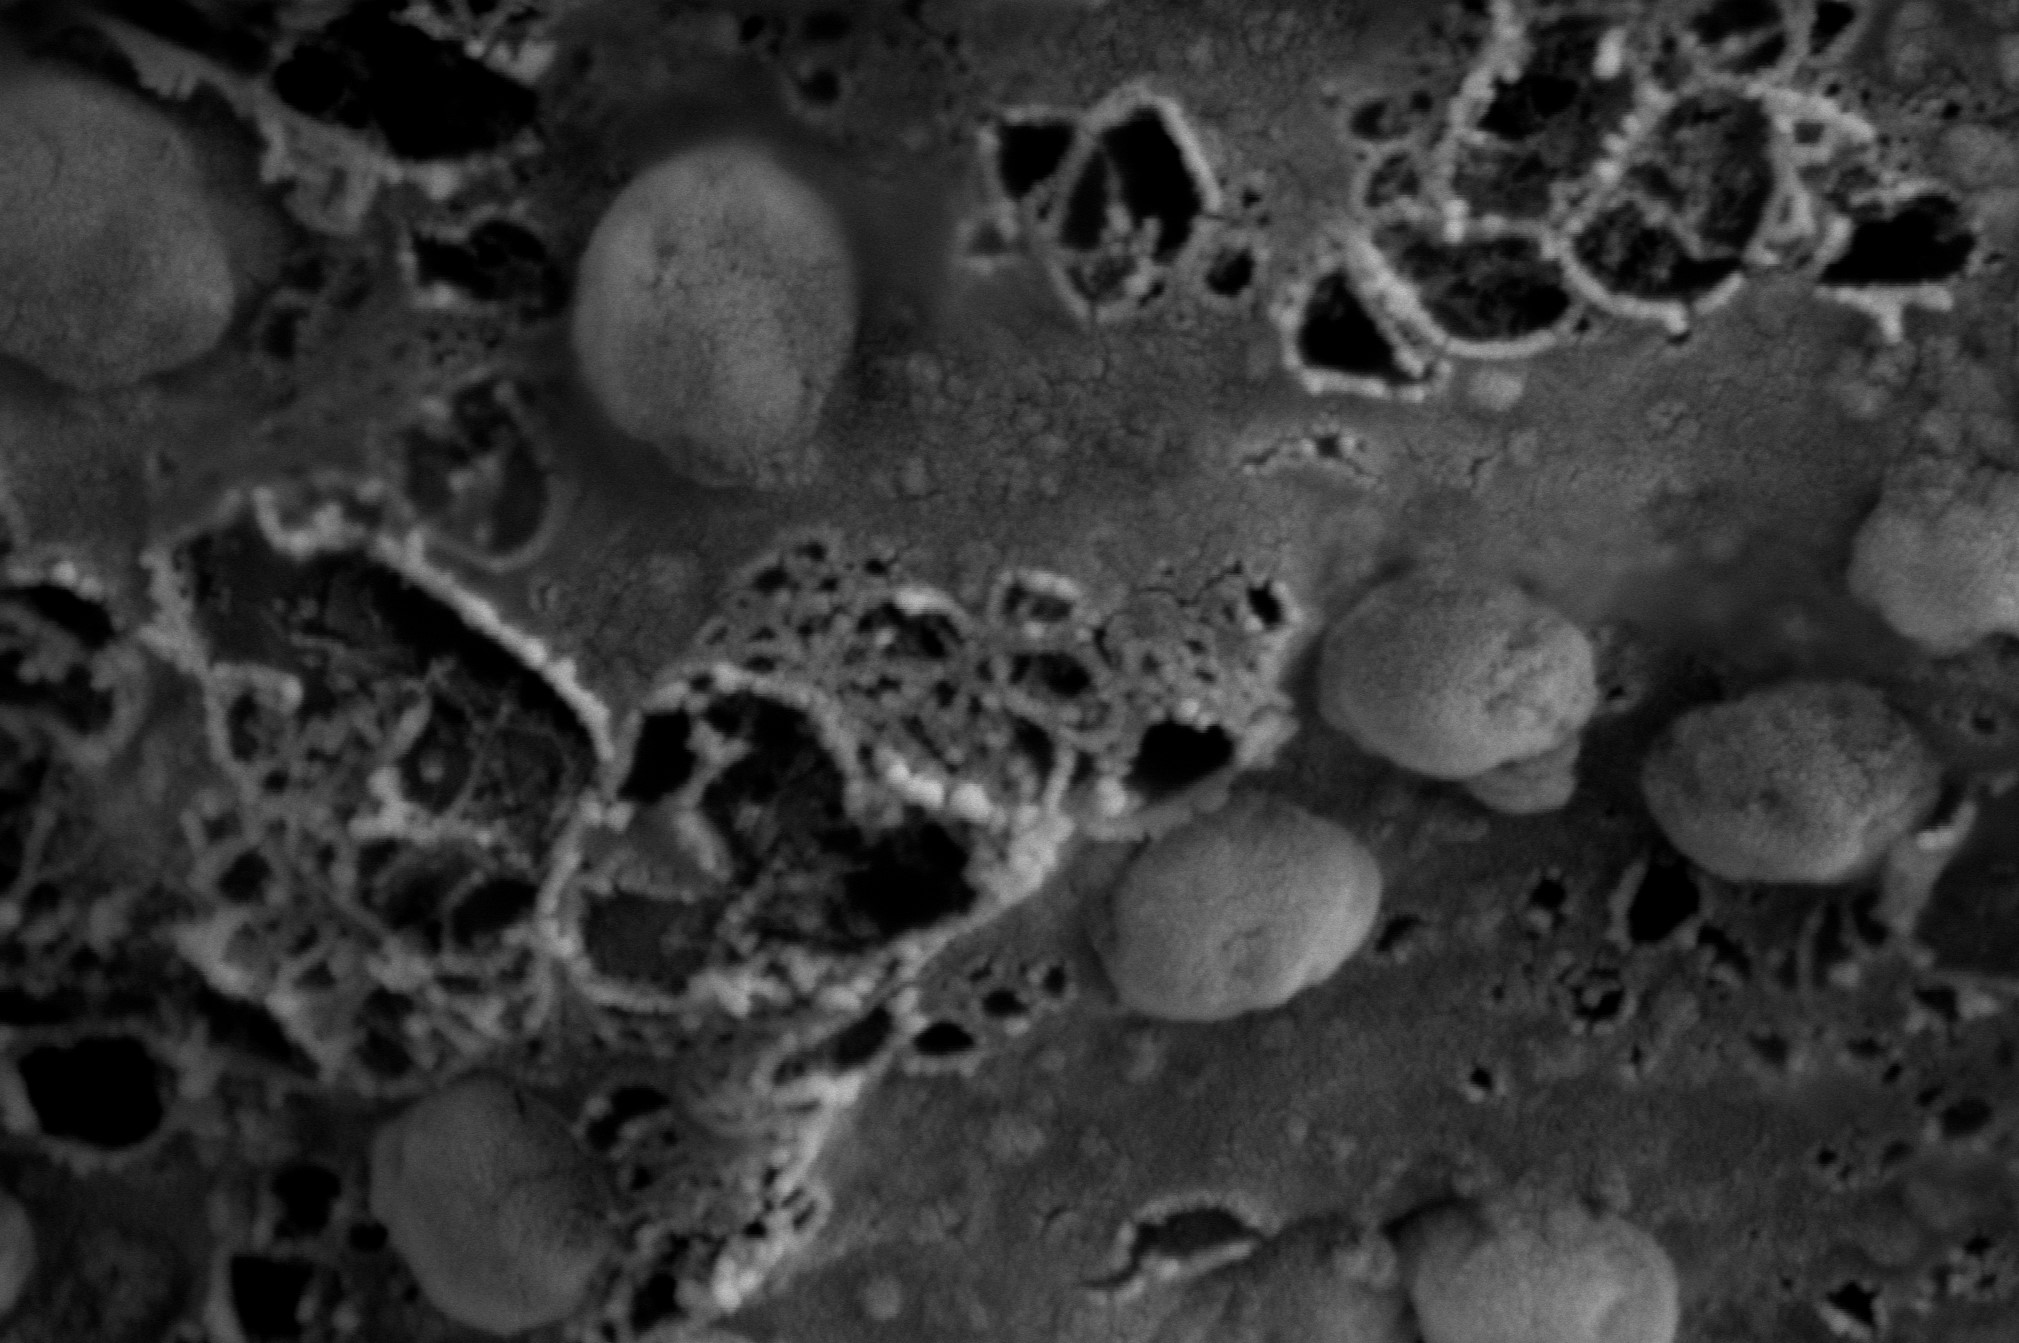

A scanning electron microscopy image are presented showing the morphology and size of the anti-viral exosomes

In a mouse study, scientists developed an anti-HIV protein called ZPAMt that can be delivered to affected areas using exosomes nanosized parts of cells able to reach difficult-to-access areas of the body, such as the brain.